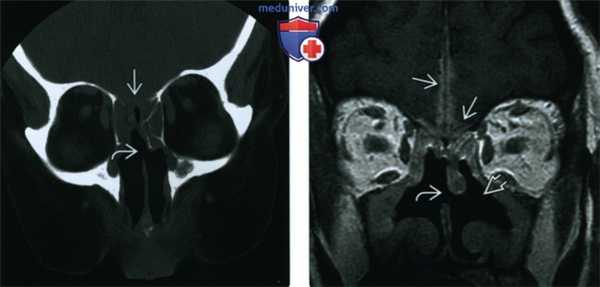

(Слева) При корональной КТ у пациента с ГПА, хроническим риносинуситом и жалобами на головную боль определяется перфорация носовой перегородки, а также сливное снижение пневматизации решетчатых пазух с обеих сторон в сочетании с деструкцией решетчатой пластинки.

(Справа) При корональной МРТ у этого же пациента определяется диффузное утолщение слизистой оболочки верхнечелюстных и решетчатых пазух, перфорация носовой перегородки, двухсторонняя деструкция носовых раковин и наружных стенок носовой полости. Обратите внимание на контактный лахименингит передней черепной ямки.